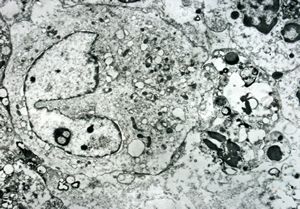

M,71y. | blood - blastic elements